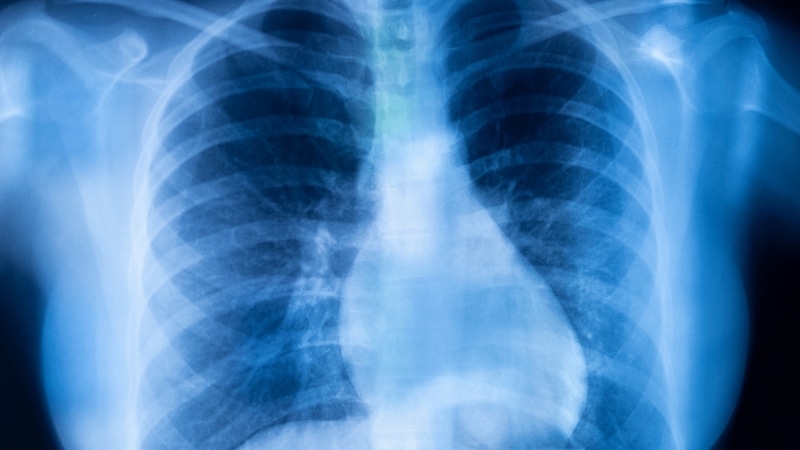

KOAH Her 5 Yetişkinden Birini Tehdit Ediyor: Bu Belirtiler Görmezden Gelinmemeli

Uzmanlara göre Türkiye'de 40 yaş üzeri her beş yetişkinden biri KOAH riski taşıyor. Hastalığın erken belirtileri çoğu zaman göz ardı edildiği için teşhis gecikiyor.

Dünya genelinde milyonlarca insanı etkileyen KOAH, her yıl milyonlarca kişinin ölümüne yol açarak tüm ölüm nedenleri arasında üst sıralara yerleşiyor.